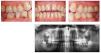

El cuadro clínico característico de la periodontitis del fumador incluye una encía marginal relativamente pálida con pocos signos inflamatorios y profundidades de sondaje superiores a 4 mm, sobre todo en zonas interproximales que, sin embargo, muestran poca tendencia al sangrado durante el sondaje periodontal (figs. 4a-4d).

Figuras 4a-4d. Imagen clínica intraoral e imagen radiológica de una periodontitis de fumador crónica avanzada. Llama la atención la encía marginal con hipertrofia fibrosa que muestra una respuesta pobre al estímulo bacteriano, y los signos radiológicos de una pérdida ósea marcada en el sector posterior. El paciente tiene 46 años y fuma 10-20 cigarrillos al día desde hace aproximadamente 25 años, lo que corresponde a alrededor de 20 años-paquete. Las imágenes intraorales se obtuvieron después de la extracción de los dientes 37 y 47 practicada de urgencia (abscesos periodontales).